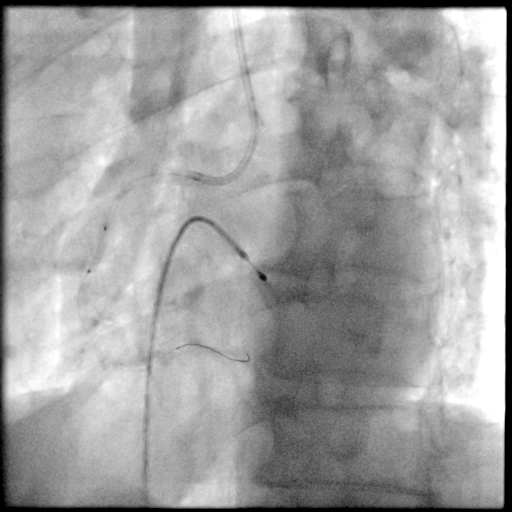

冠脉造影

PCI过程-球囊PTCA

预置临时起搏器后,7F AL1.0无法到位,更换为7F SAL1.0至RCA开口,应用非顺应性球囊2.5X15mm,于RCA中段病变处以12-18atm扩张,球囊膨胀不佳。